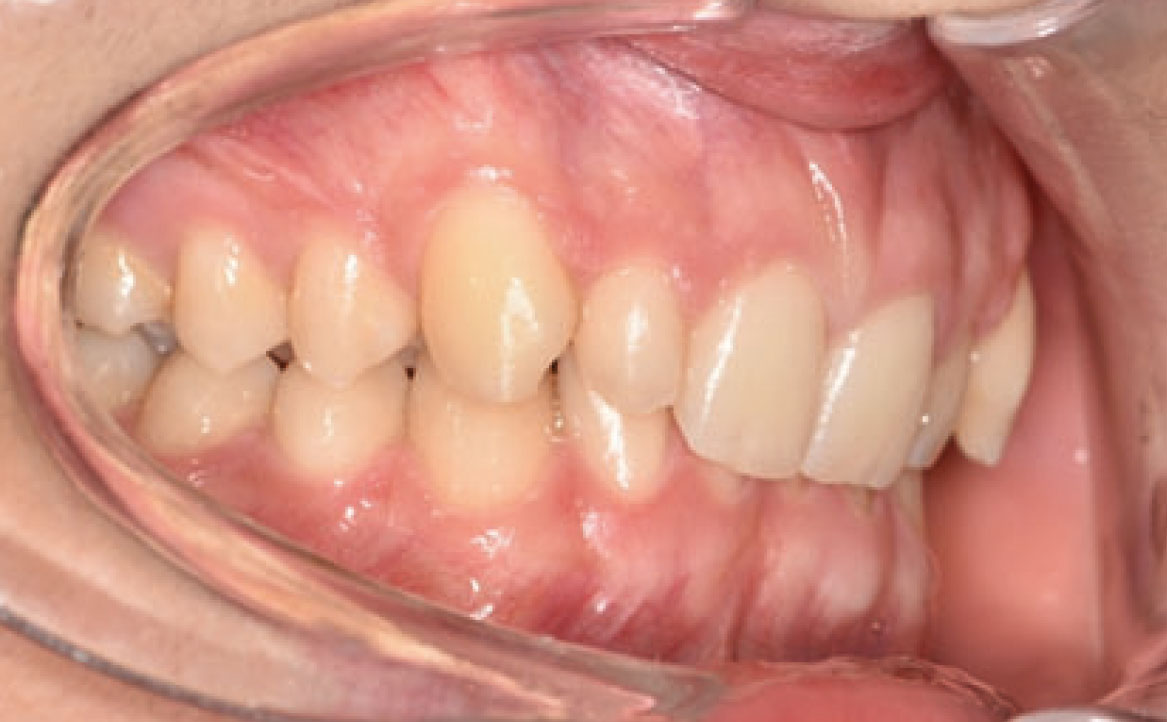

Il paziente si è presentato per la sua prima visita presso il reparto di Odontoiatria e Protesi Dentaria dell’Ospedale Vita-Salute San Raffaele diretto dal prof. E. F. Gherlone. All’esame obiettivo era evidente una malocclusione scheletrica e dentale di classe II associata a morso profondo e lieve affollamento anteriore superiore. In particolare, sono stati segnalati: rapporti occlusali di classe II, morso profondo, perdita di overjet, contrazione dell’arcata superiore e inferiore con leggero affollamento (fig. 1a-f). La richiesta del paziente era quella di migliorare l’estetica dei denti anteriori con allineatori invisibili di tipo Invisalign. Tuttavia, sia il paziente che il genitore sono stati informati che, per ragioni di efficacia e risoluzione del problema, era necessario agire anche a livello di funzionalità e risoluzione della malocclusione.

In primo luogo, sono stati prescritti entrambi gli esami radiografici ortodontici: OPT e teleradiografia latero-laterale del cranio (fig. 2a-b). Successivamente, in accordo con il genitore, è stata concordata una terapia ortodontica in due tempi. L’inizio della terapia è stato effettuato con Carriere Motion ed elastici di classe II, con l’obiettivo di migliorare la classe molare (fig. 2c-e).

Infatti, durante il primo controllo due mesi dopo, è stato osservato un miglioramento della classe molare (fig. 3a-c).